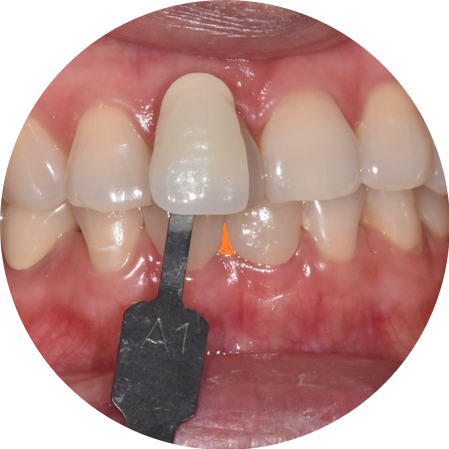

230703

오늘 환자분도 2번의 미백을 통해

기존 A2 색상을 A1까지 만든 후

라미네이트 제작을 진행했습니다.